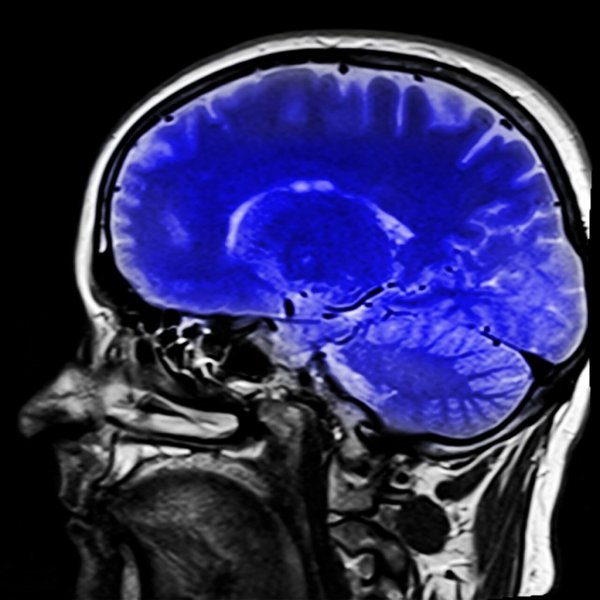

There are neurological tests that help doctors diagnose this syndrome. MRI’s can show what kind of stroke happened, and this will help them determine what it is.